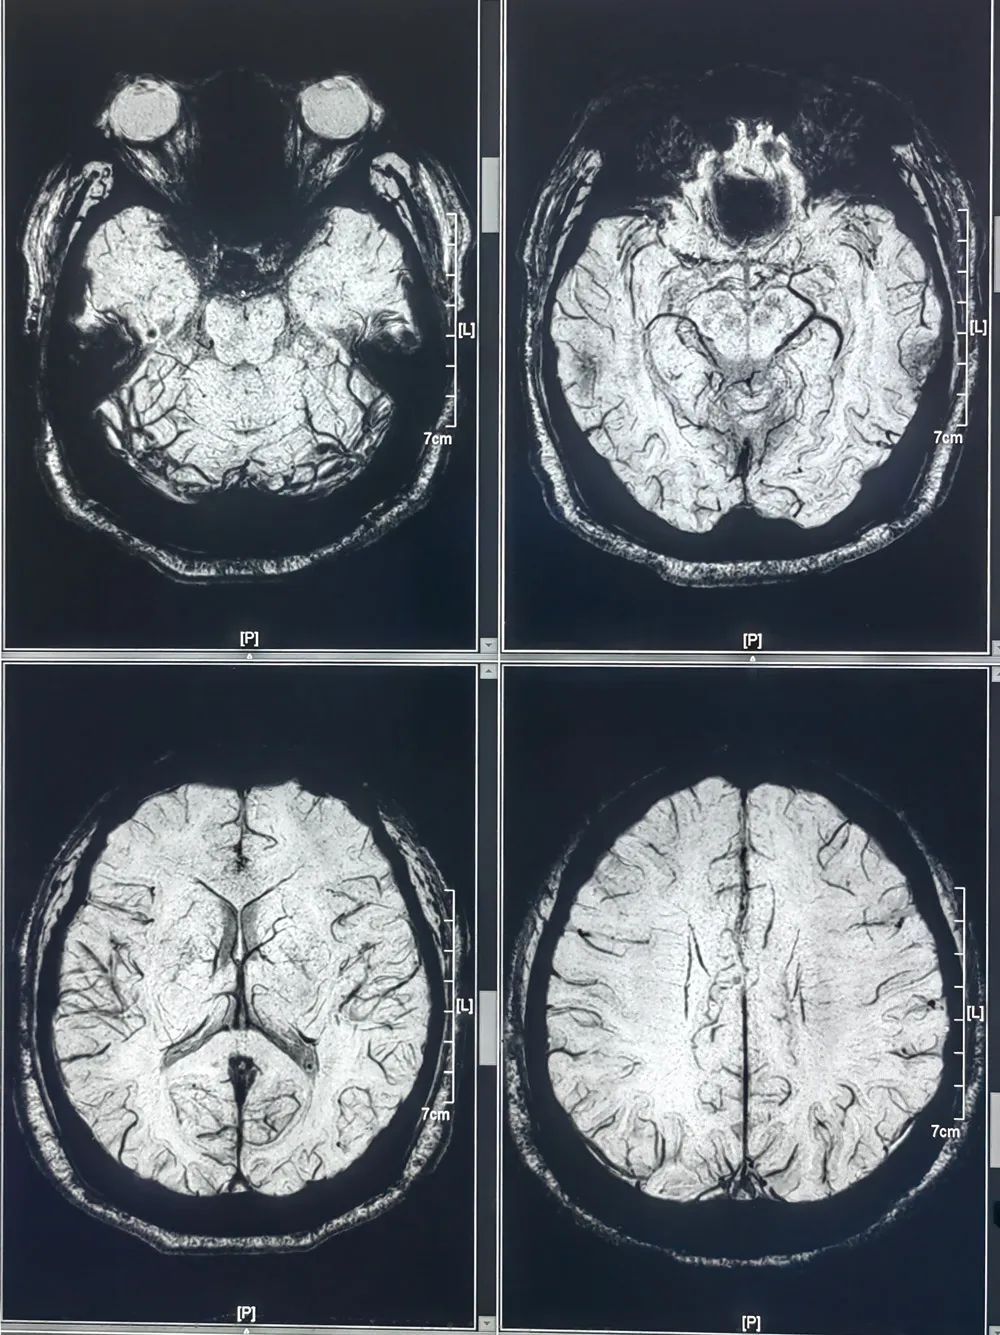

磁敏感成像(SWI)

磁敏感加权成像(SWI)是对磁场均匀性改变的信号采集非常敏感的三维采集成像序列,具有高分辨率、高信噪比的磁共振成像(MRI)三维成像技术,越来越多的用于神经系统疾病的诊断及鉴别诊断。